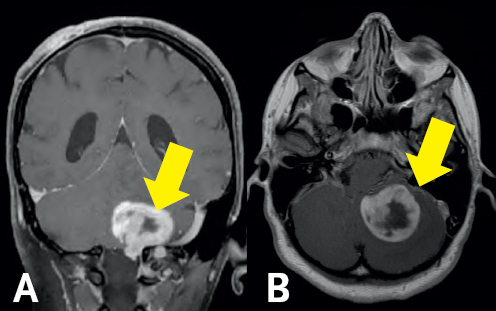

The prognosis for GBM is generally poor—the median survival is roughly 12 months after diagnosis.7 Incredibly, Jane has continued to defy all odds following the surgery. Her most recent MRI, now three and half years following the procedure, continues to demonstrate no evidence of any residual or recurrent tumor (Figure 6.2). As a cancer survivor, Jane continues in her courageous battle against NF1. Her determination in the face of adversity remains a source of inspiration for her friends, family members, and providers.

(Left) Gray colored variations are enclosed by a white outline. There is a dark gray column at the bottom of the image in the middle connecting the gray area to the bottom of the image. (Right) Gray and white colorations are depicting normal brain structures; all are surrounded by a white boarder.

FIGURE 6.2 Two-year Follow-up MRI. Post-operative coronal (A) and sagittal (B) MRI continues to demonstrate no evidence of tumor recurrence following her original gross total resection.